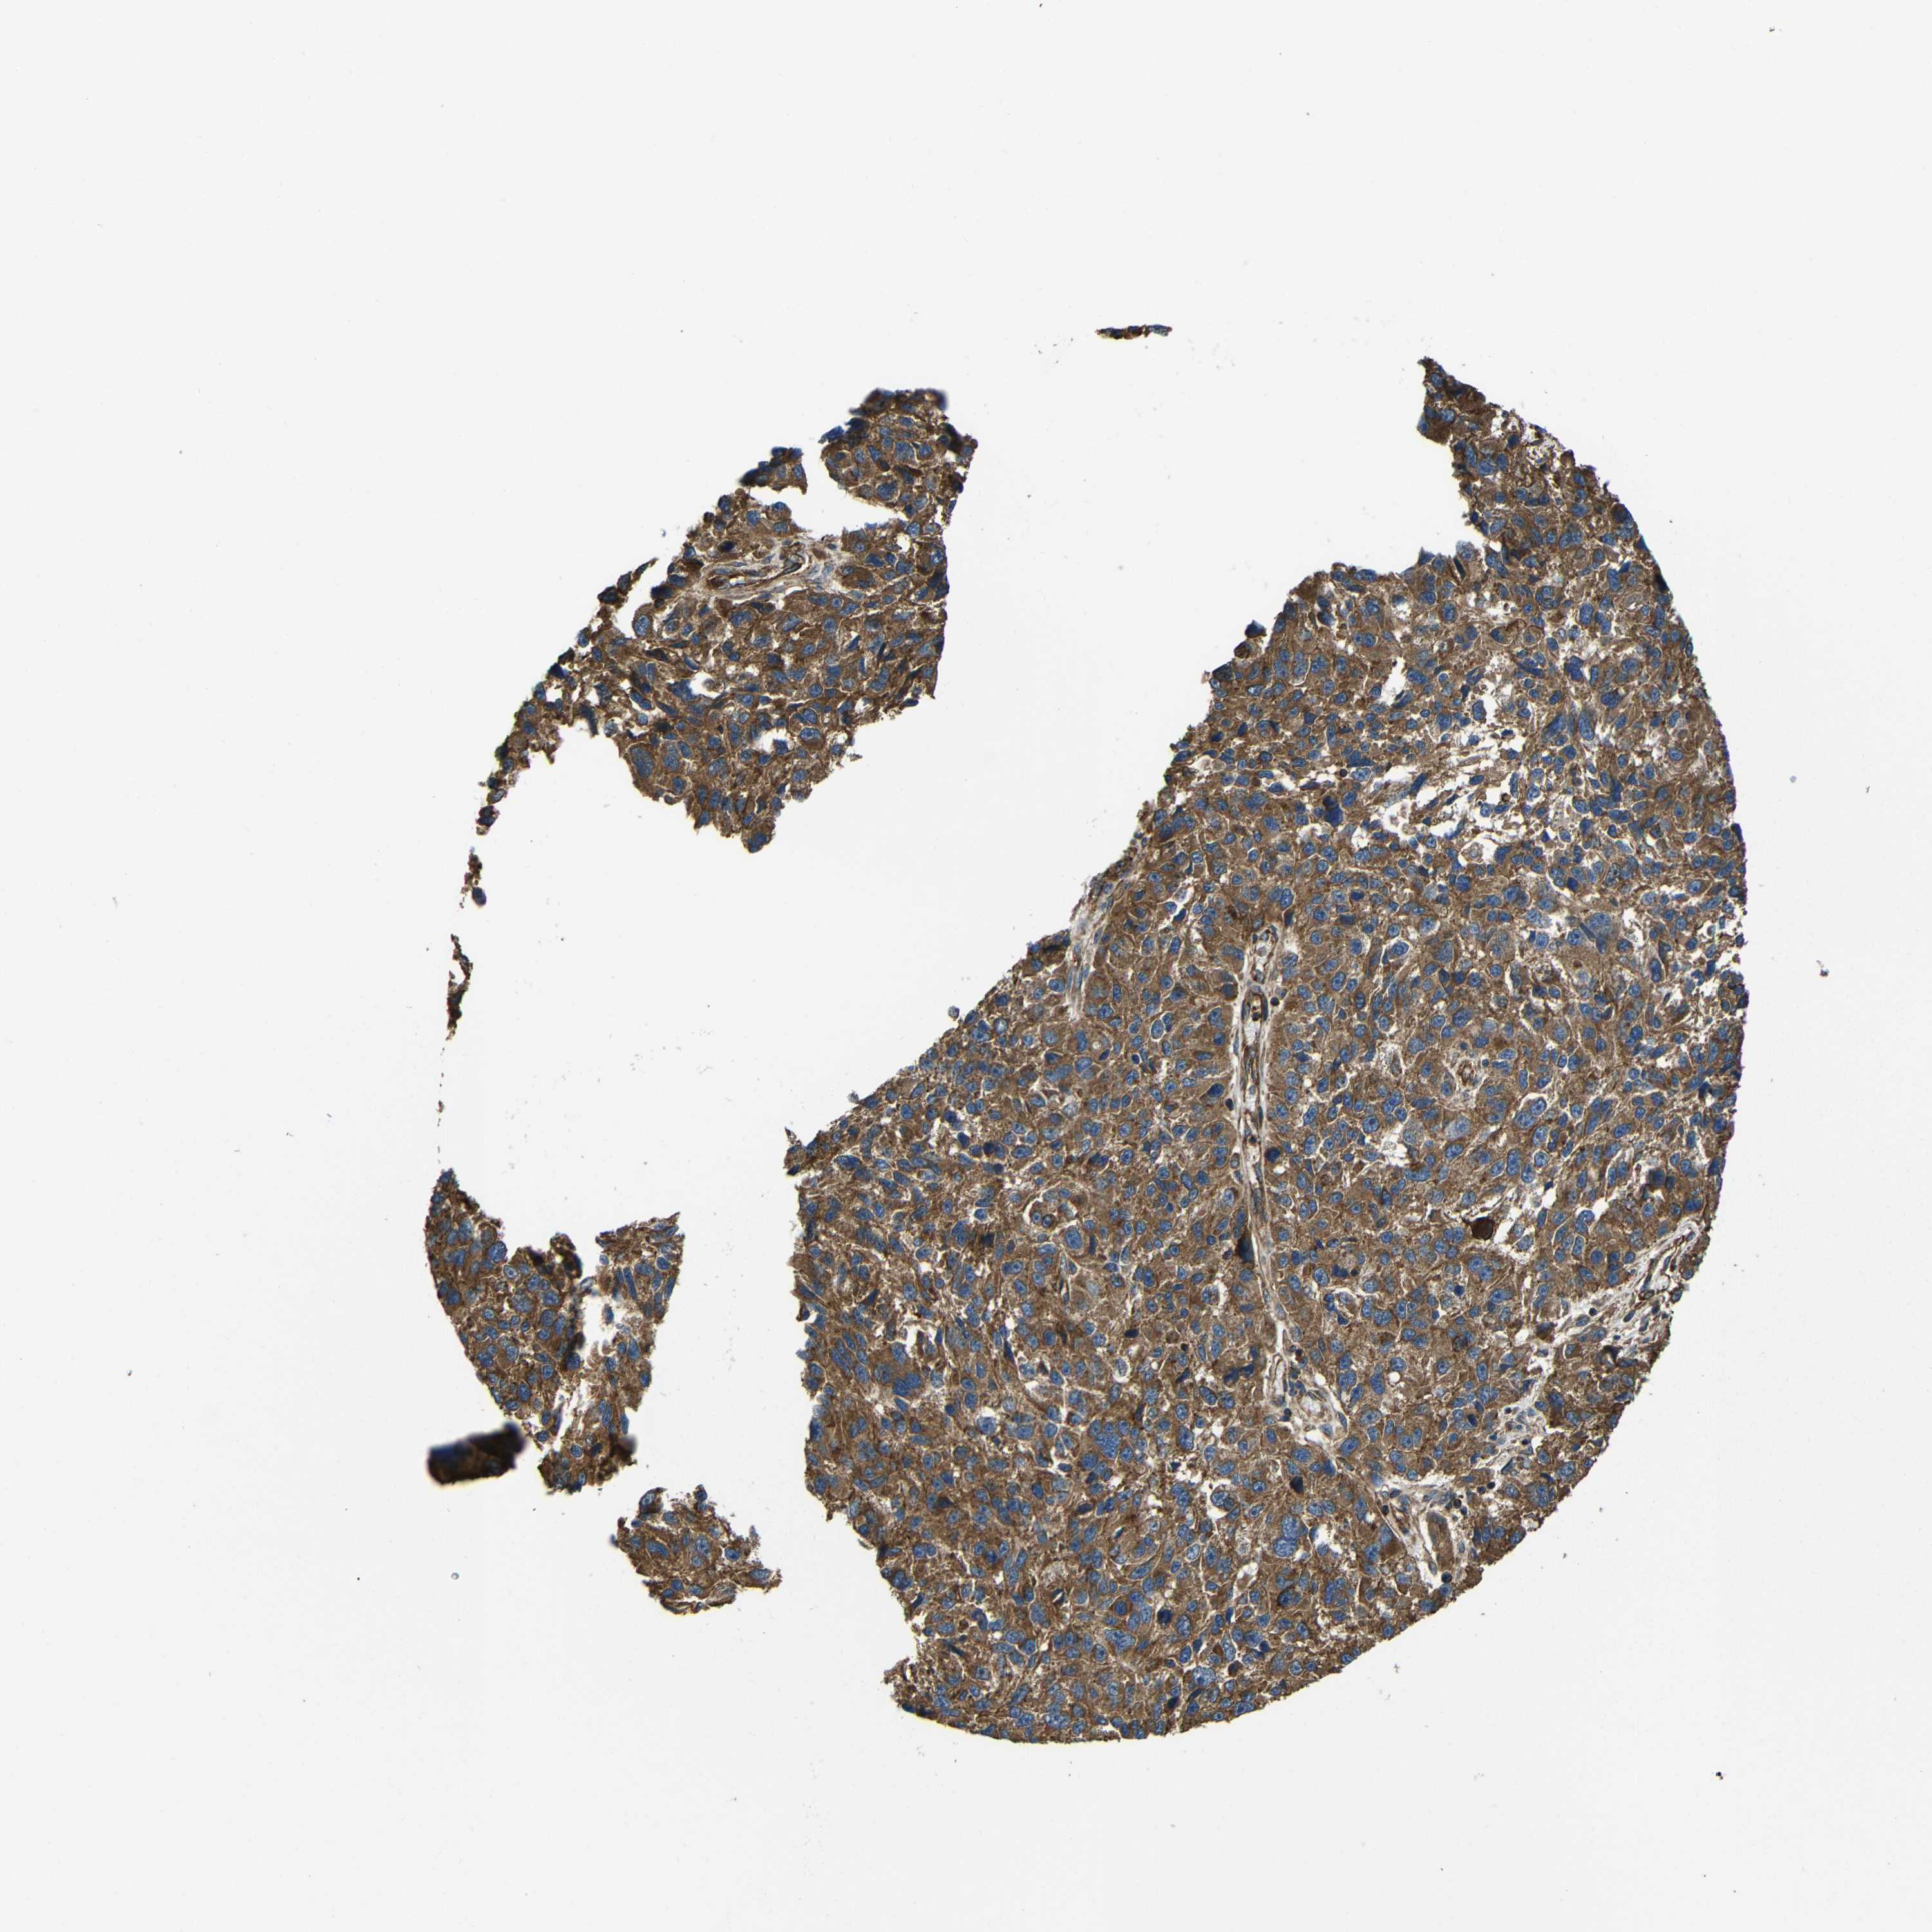

MELANOMA - Protein expressioni

A mouse-over function shows sample information and annotation data. Click on an image to view it in a full screen mode. Samples can be filtered based on level of antibody staining by selecting one or several of the following categories: high, medium, low and not detected. The assay and annotation is described here.

Note that samples used for immunohistochemistry by the Human Protein Atlas do not correspond to samples in the TCGA dataset.

Antibody stainingi

Antibody staining in the annotated cell types in the current human tissue is reported as not detected, low, medium, or high, based on conventional immunohistochemistry profiling in selected tissues. This score is based on the combination of the staining intensity and fraction of stained cells.

Each image is clickable and will lead to virtual microscopy that enables deeper exploration of all samples and also displays staining intensity scores, fraction scores and subcellular localization as well as patient and tissue information for each sample.

Antibody CAB013717

Staining

High

Medium

Low

Not detected

Intensity

Strong

Moderate

Weak

Negative

Quantity

>75%

75%-25%

<25%

None

Location

Nuclear

Cytoplasmic/membranous

Cytoplasmic/membranous,nuclear

Malignant melanoma, NOS

Malignant melanoma, Metastatic site